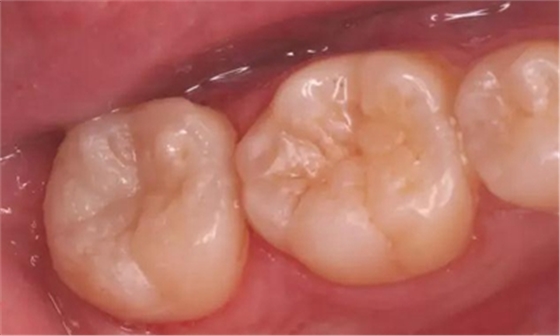

圖1 術(shù)前口內(nèi)照,37合面窩溝形態(tài)完好,

遠(yuǎn)中牙體輕度“墨浸樣”變色,探及遠(yuǎn)中齦下深齲洞

圖10 移除“印章”,合面窩溝形態(tài)得到較好復(fù)制

光固化,完成充填,調(diào)合、拋光